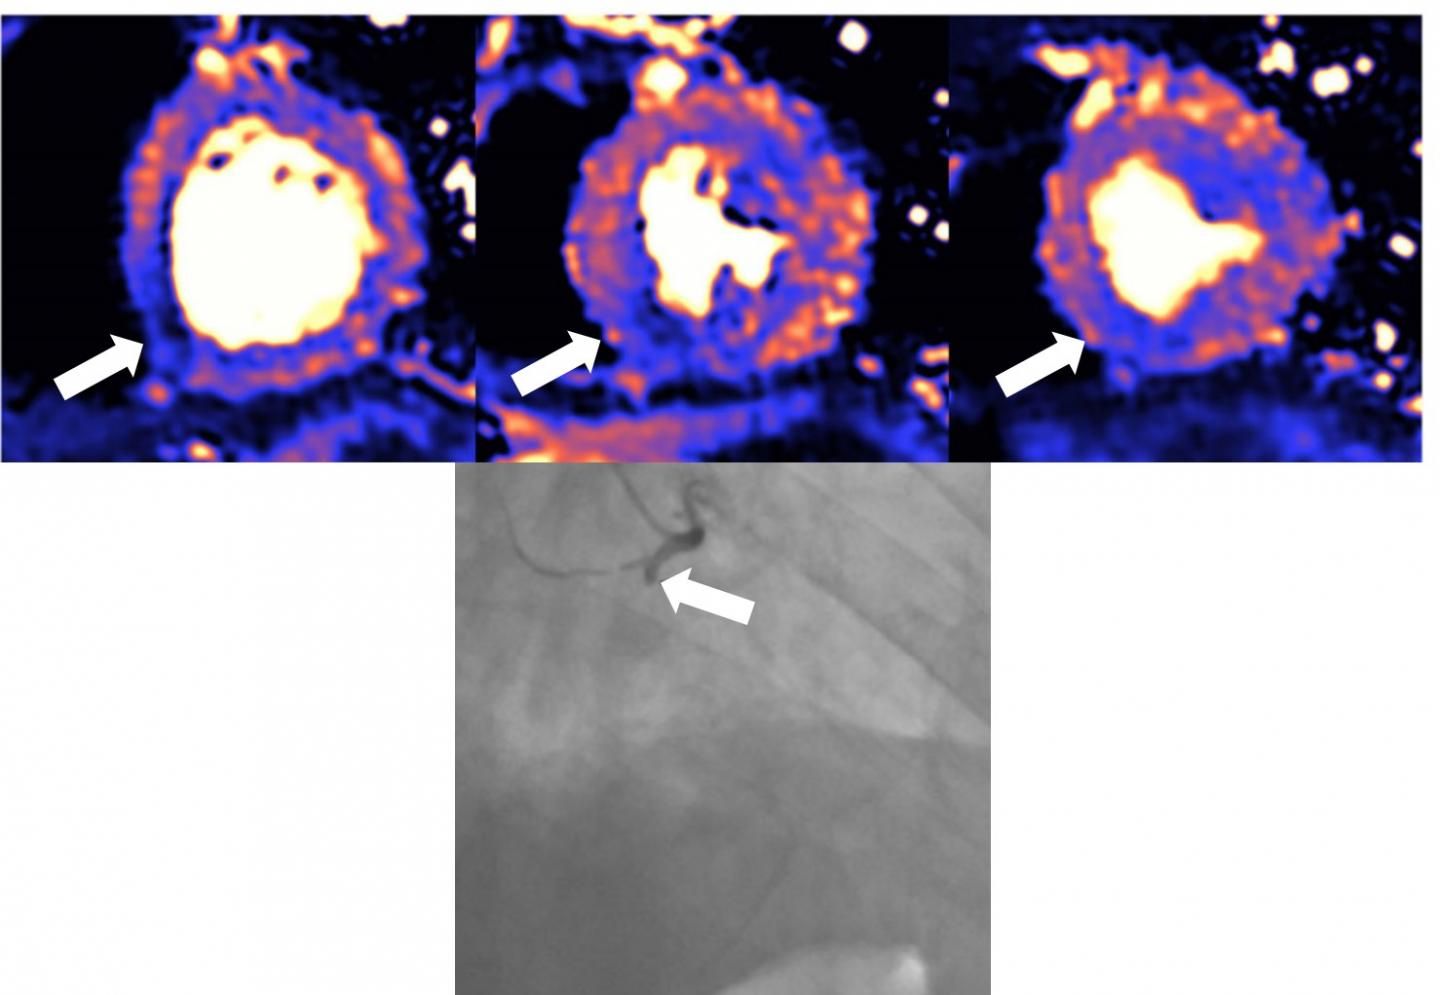

MRI scans reveal myocarditis, scarring, infarction, and ischemia in recovered patients with elevated troponin levels.

Scans identify evidence of the condition in 15 percent of athletes who have rebounded from viral infection.

Scans show cardiovascular impact lingers after the acute phase of viral infection and into recovery.